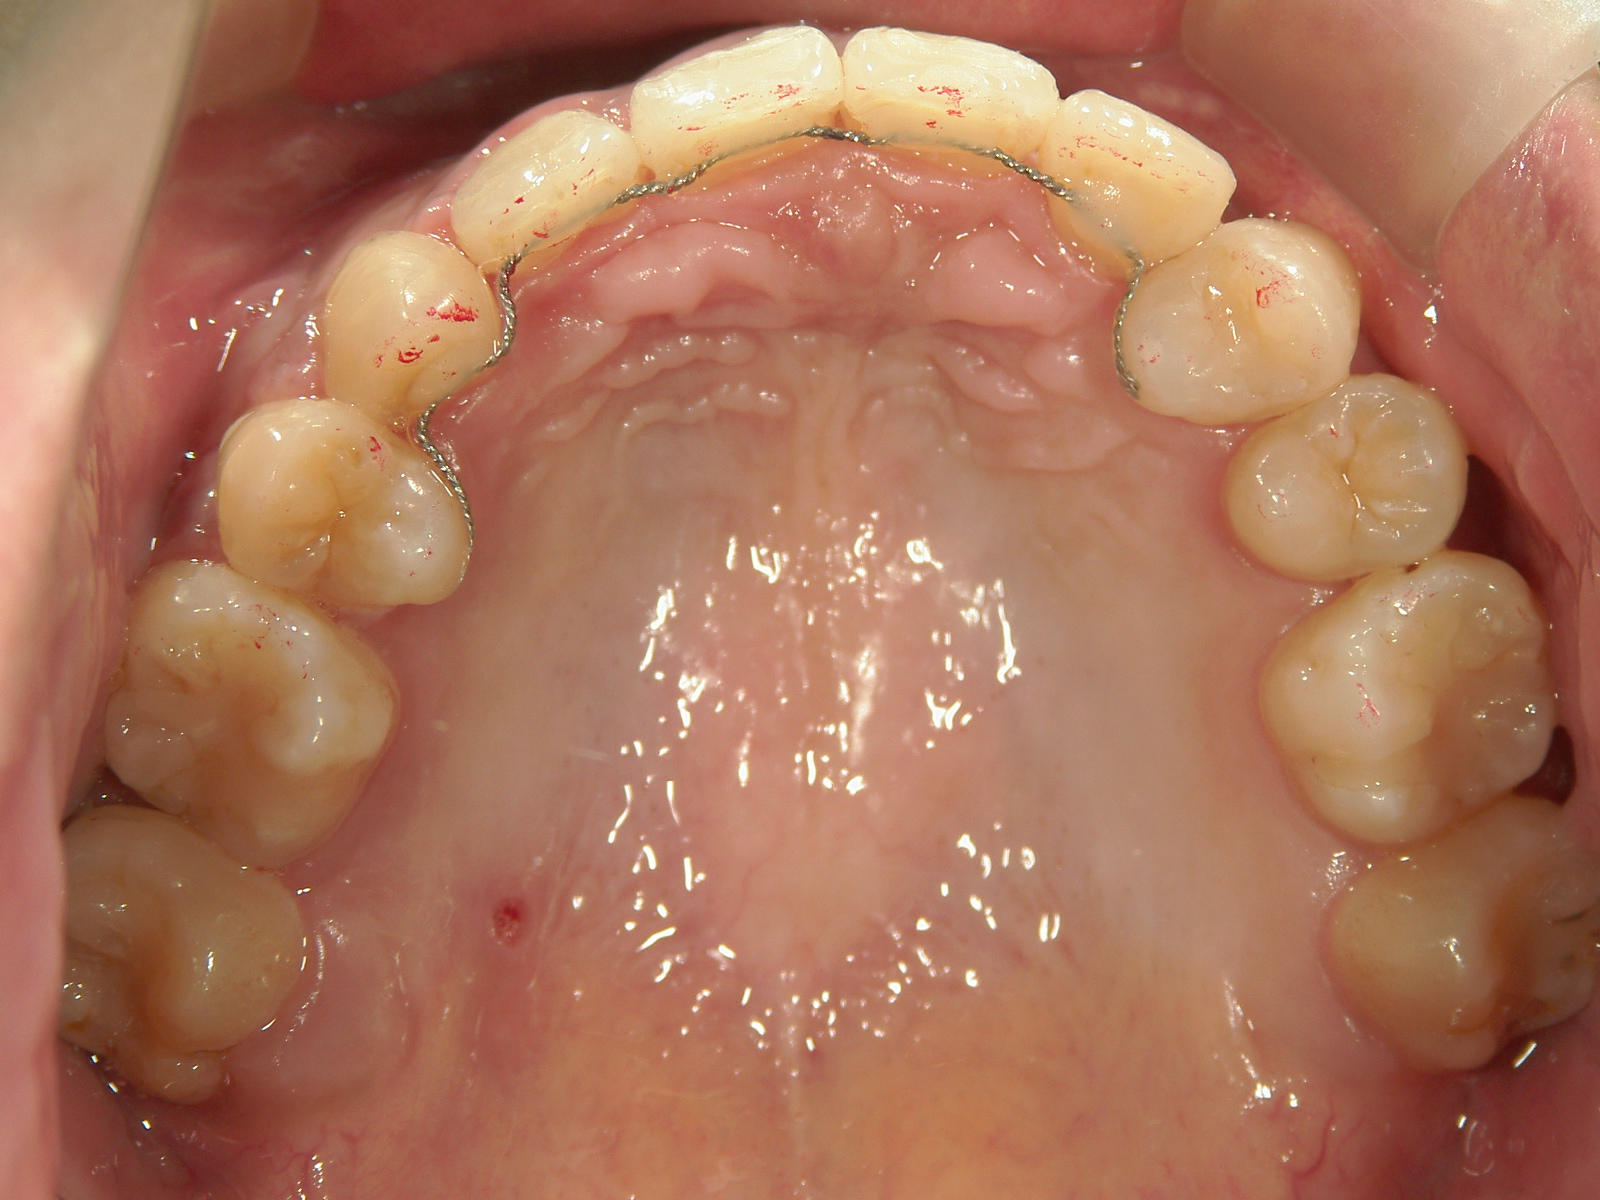

全顎ワイヤー矯正 症例(6)

主訴: 噛み合わせが悪い

①叢生を改善しました。

カテゴリー : ガタガタ(叢生) , 噛み合わせが深い(過蓋咬合)